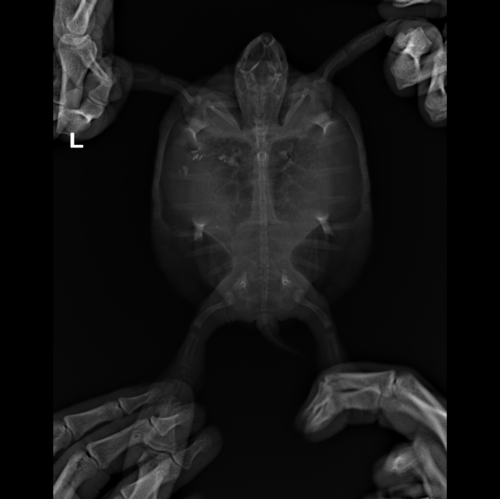

Анастасия- Ваше имя: Анастасия Локация: Ереван Опубликовано: 18 января 2022 Автор Опубликовано: 18 января 2022 Вот такой у нас сегодняшний рентген, врач сказала продолжать антибиотик, прийти на повторный анализ крови а вот это рентген от 4 января перед курсом антибиотиков и уколами Элеовита:

Консультанты moth Ваше имя: Мария Локация: Москва Опубликовано: 18 января 2022 Консультанты Опубликовано: 18 января 2022 @Анастасия- по лёгким тут явно лучше на сколько я могу читать снимки - по-моему там есть скопление газов, что и могло приводить к тому, что Вы описывали. Врач ничего не говорила про это?

Анастасия- Ваше имя: Анастасия Локация: Ереван Опубликовано: 18 января 2022 Автор Опубликовано: 18 января 2022 @moth врач сказала, что в кишечнике много газов, пока ждать что будет дальше, и что кусочков инородных больше не видно. Сегодня делали у врача укол Элеовита, а вечером уже я делала антибиотик, и черепашка обмочилась очень желтым, такого яркого раньше не было - наверное из-за витаминов? Сегодня черепашка довольно подвижная, то плавает, то на островке сидит, но кушать пока отказывается

Консультанты moth Ваше имя: Мария Локация: Москва Опубликовано: 18 января 2022 Консультанты Опубликовано: 18 января 2022 @Анастасия- да, цвет из-за витаминов. Ну будем надеяться, что всё будет хорошо. Газы сильно сдавливают лёгкие и другие органы, черепахе больно и не комфортно, поэтому так себя вела.